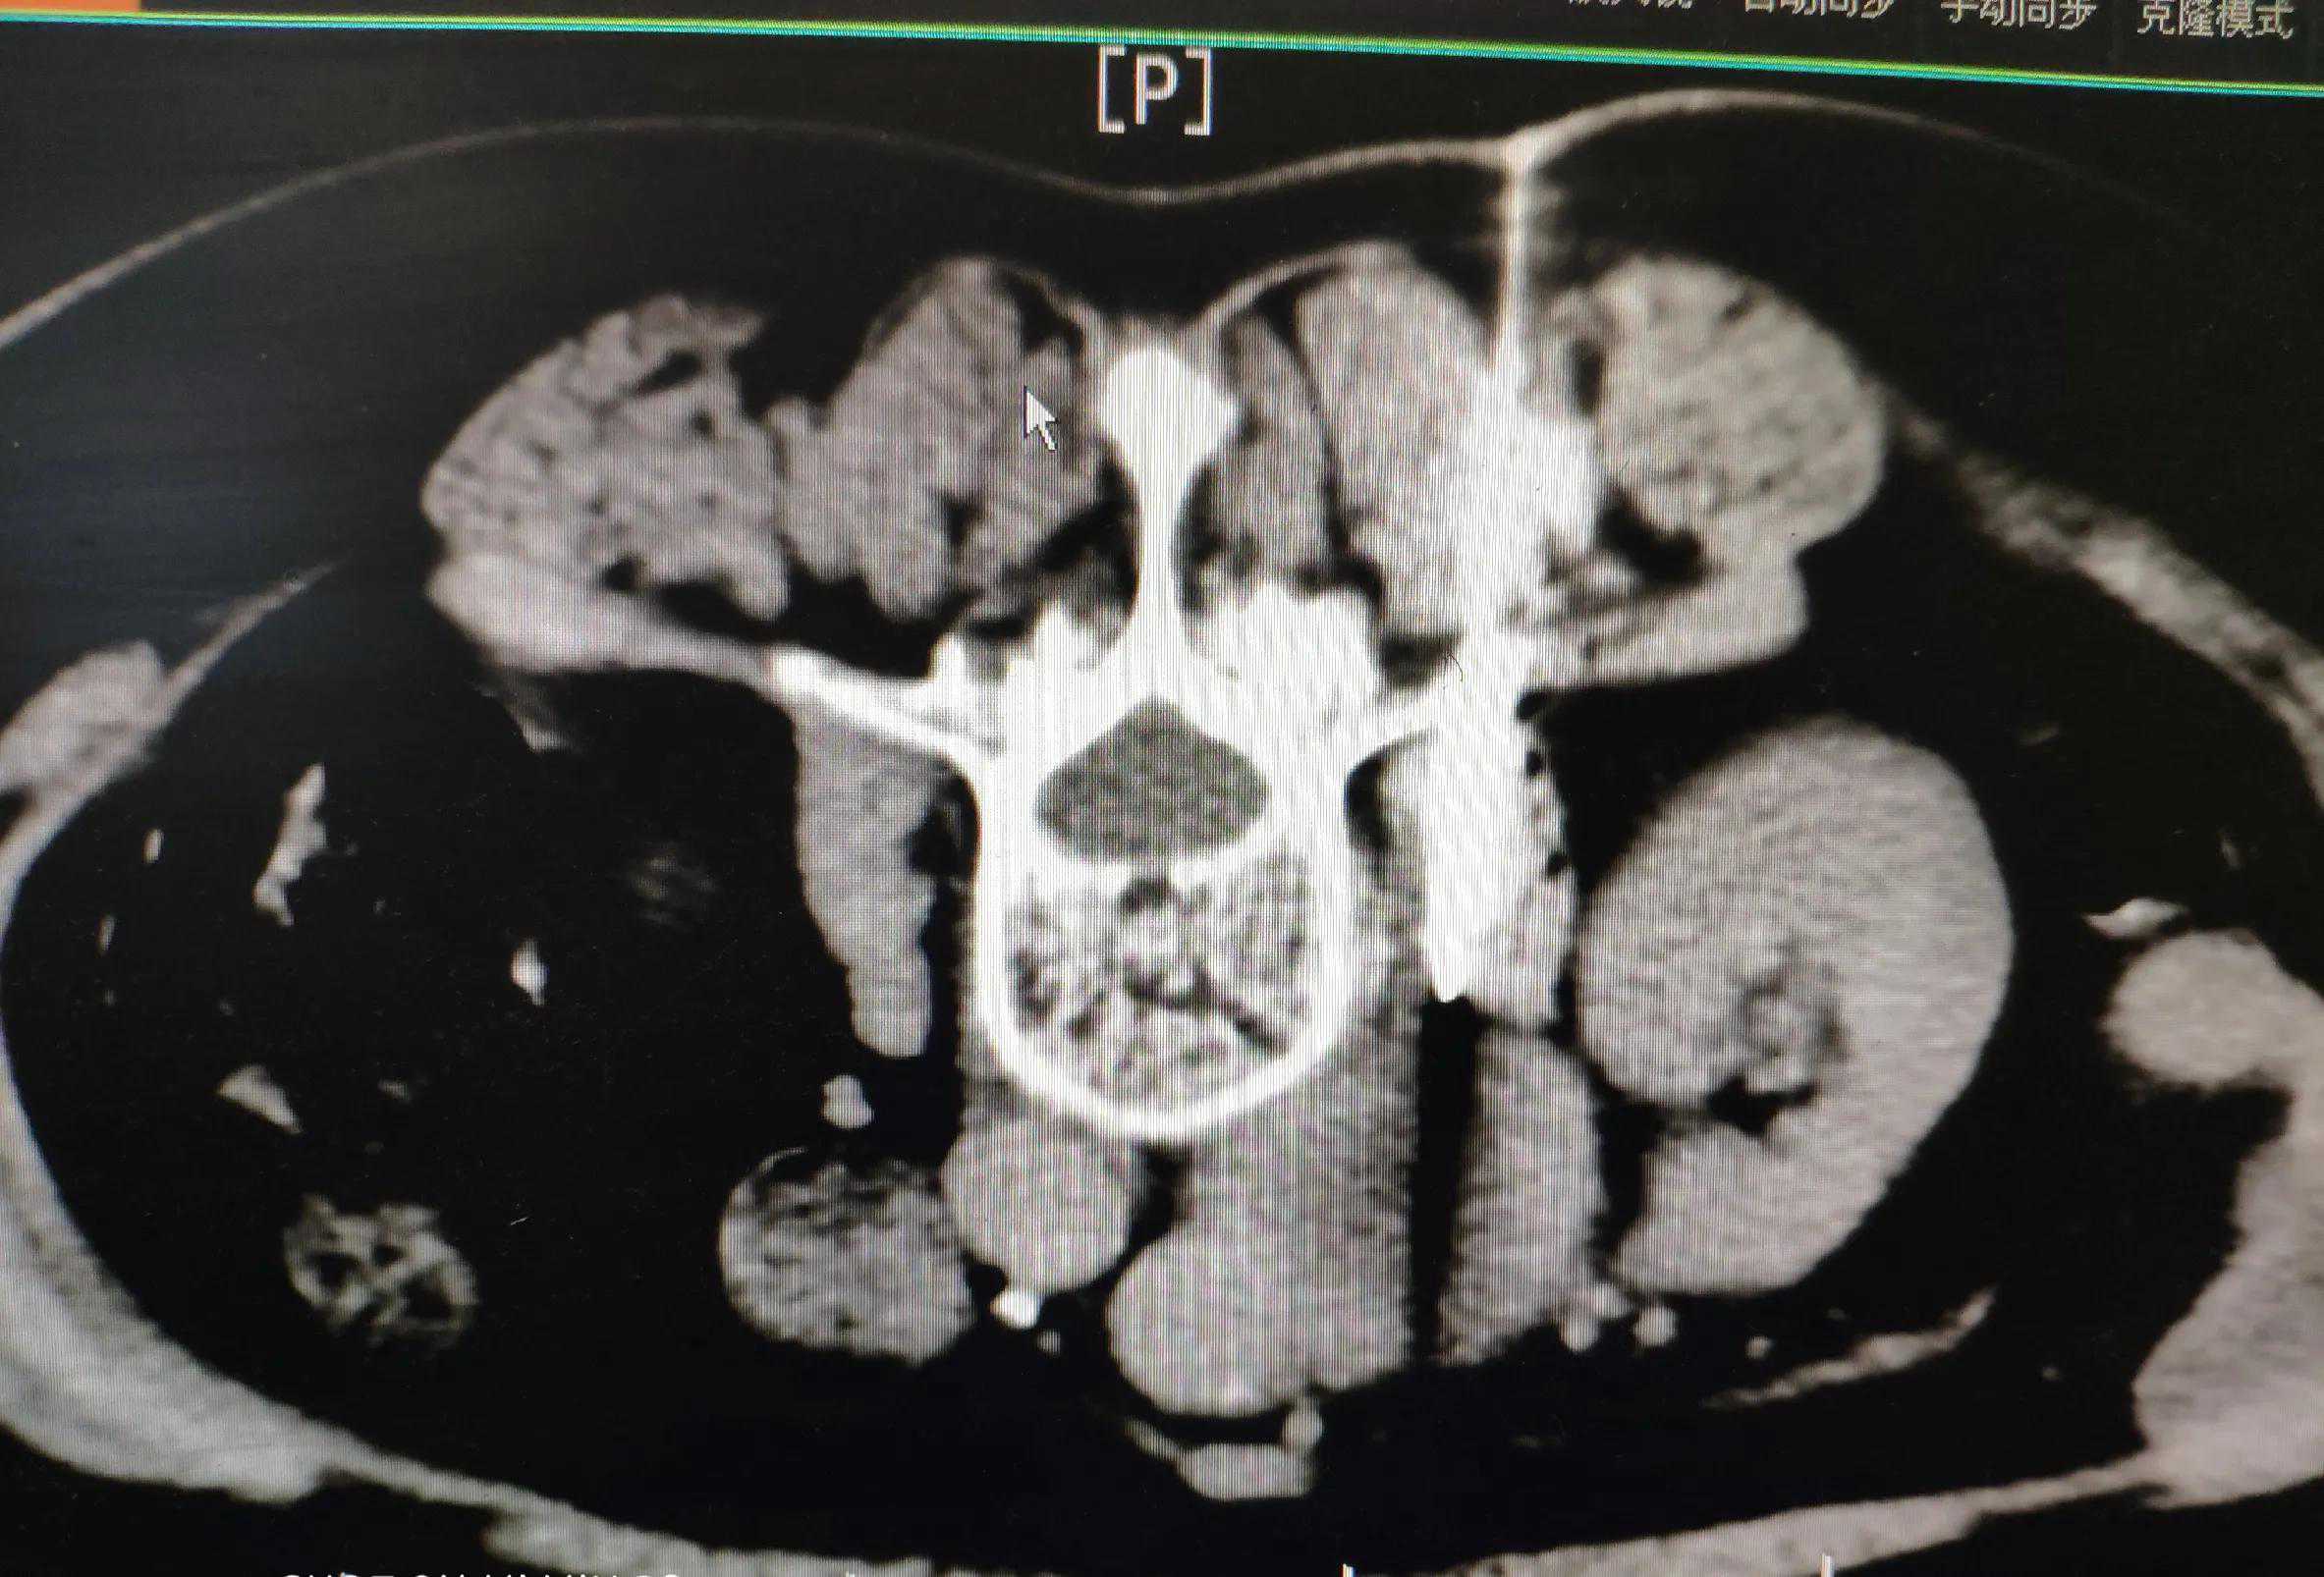

CT显示的肿瘤

PET-CT:腹膜后腹主动脉旁、髂血管旁、心隔区多发淋巴结肿大,上腹部者中央明显坏死,考虑恶性肿瘤转移。

病理:多条坏死物,纤维组织中见高度异型上皮细胞巢,考虑为转移性低分化癌。